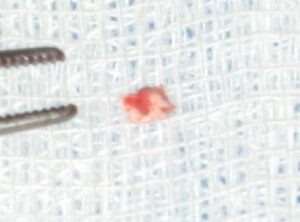

外科的根管治療を行う。出てきた異物はユージノールが固化したものと思われた。

【摘出した異物】